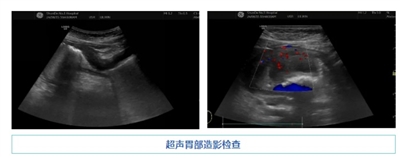

2024-09-13女子胸痛胸悶入院治療,超聲胃部造影后發(fā)現(xiàn)“元兇”竟是...

“醫(yī)生,很感謝你救了我老婆的命,真的!”近日,超聲科多次收到吳先生發(fā)來的致謝信息。原來,吳先生的妻子因“胸痛、胸悶10余天,咯血半天”,入住我院呼吸與危重癥醫(yī)學(xué)科治療。8月15日,李女士在超聲科接受肝膽脾胰超聲檢查,接診醫(yī)生李萍蘭為患者探查...閱讀全文